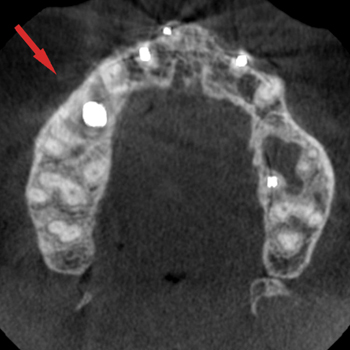

Avant : la largueur osseuse est faible, un implant trop étroit pourrait être placé dans un axe incompatible avec un bon résultat esthétique

Après : la largueur osseuse est normale, un implant de diamètre adapté est placé dans l’axe idéal pour un bon résultat esthétique et pérenne